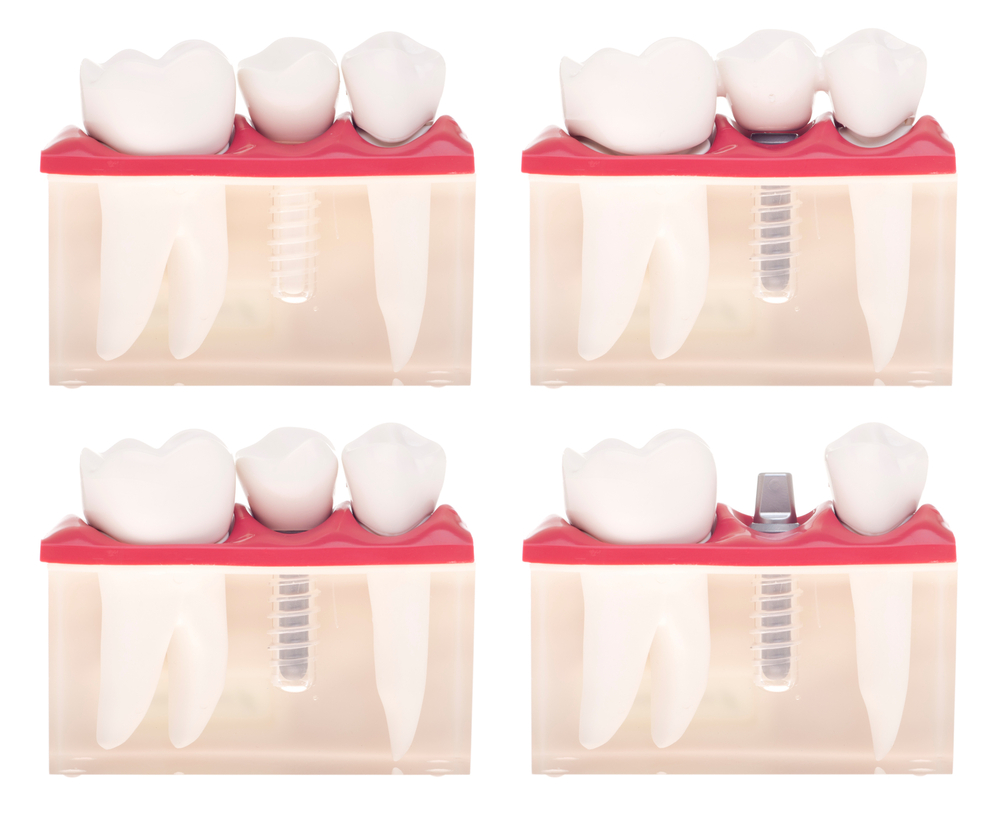

Types of dental crown and caps

Crowns and caps are basically fixed prosthetics objects which are cemented and drilled into a tooth so as to fill it. The four different types of crowns and caps are as follows